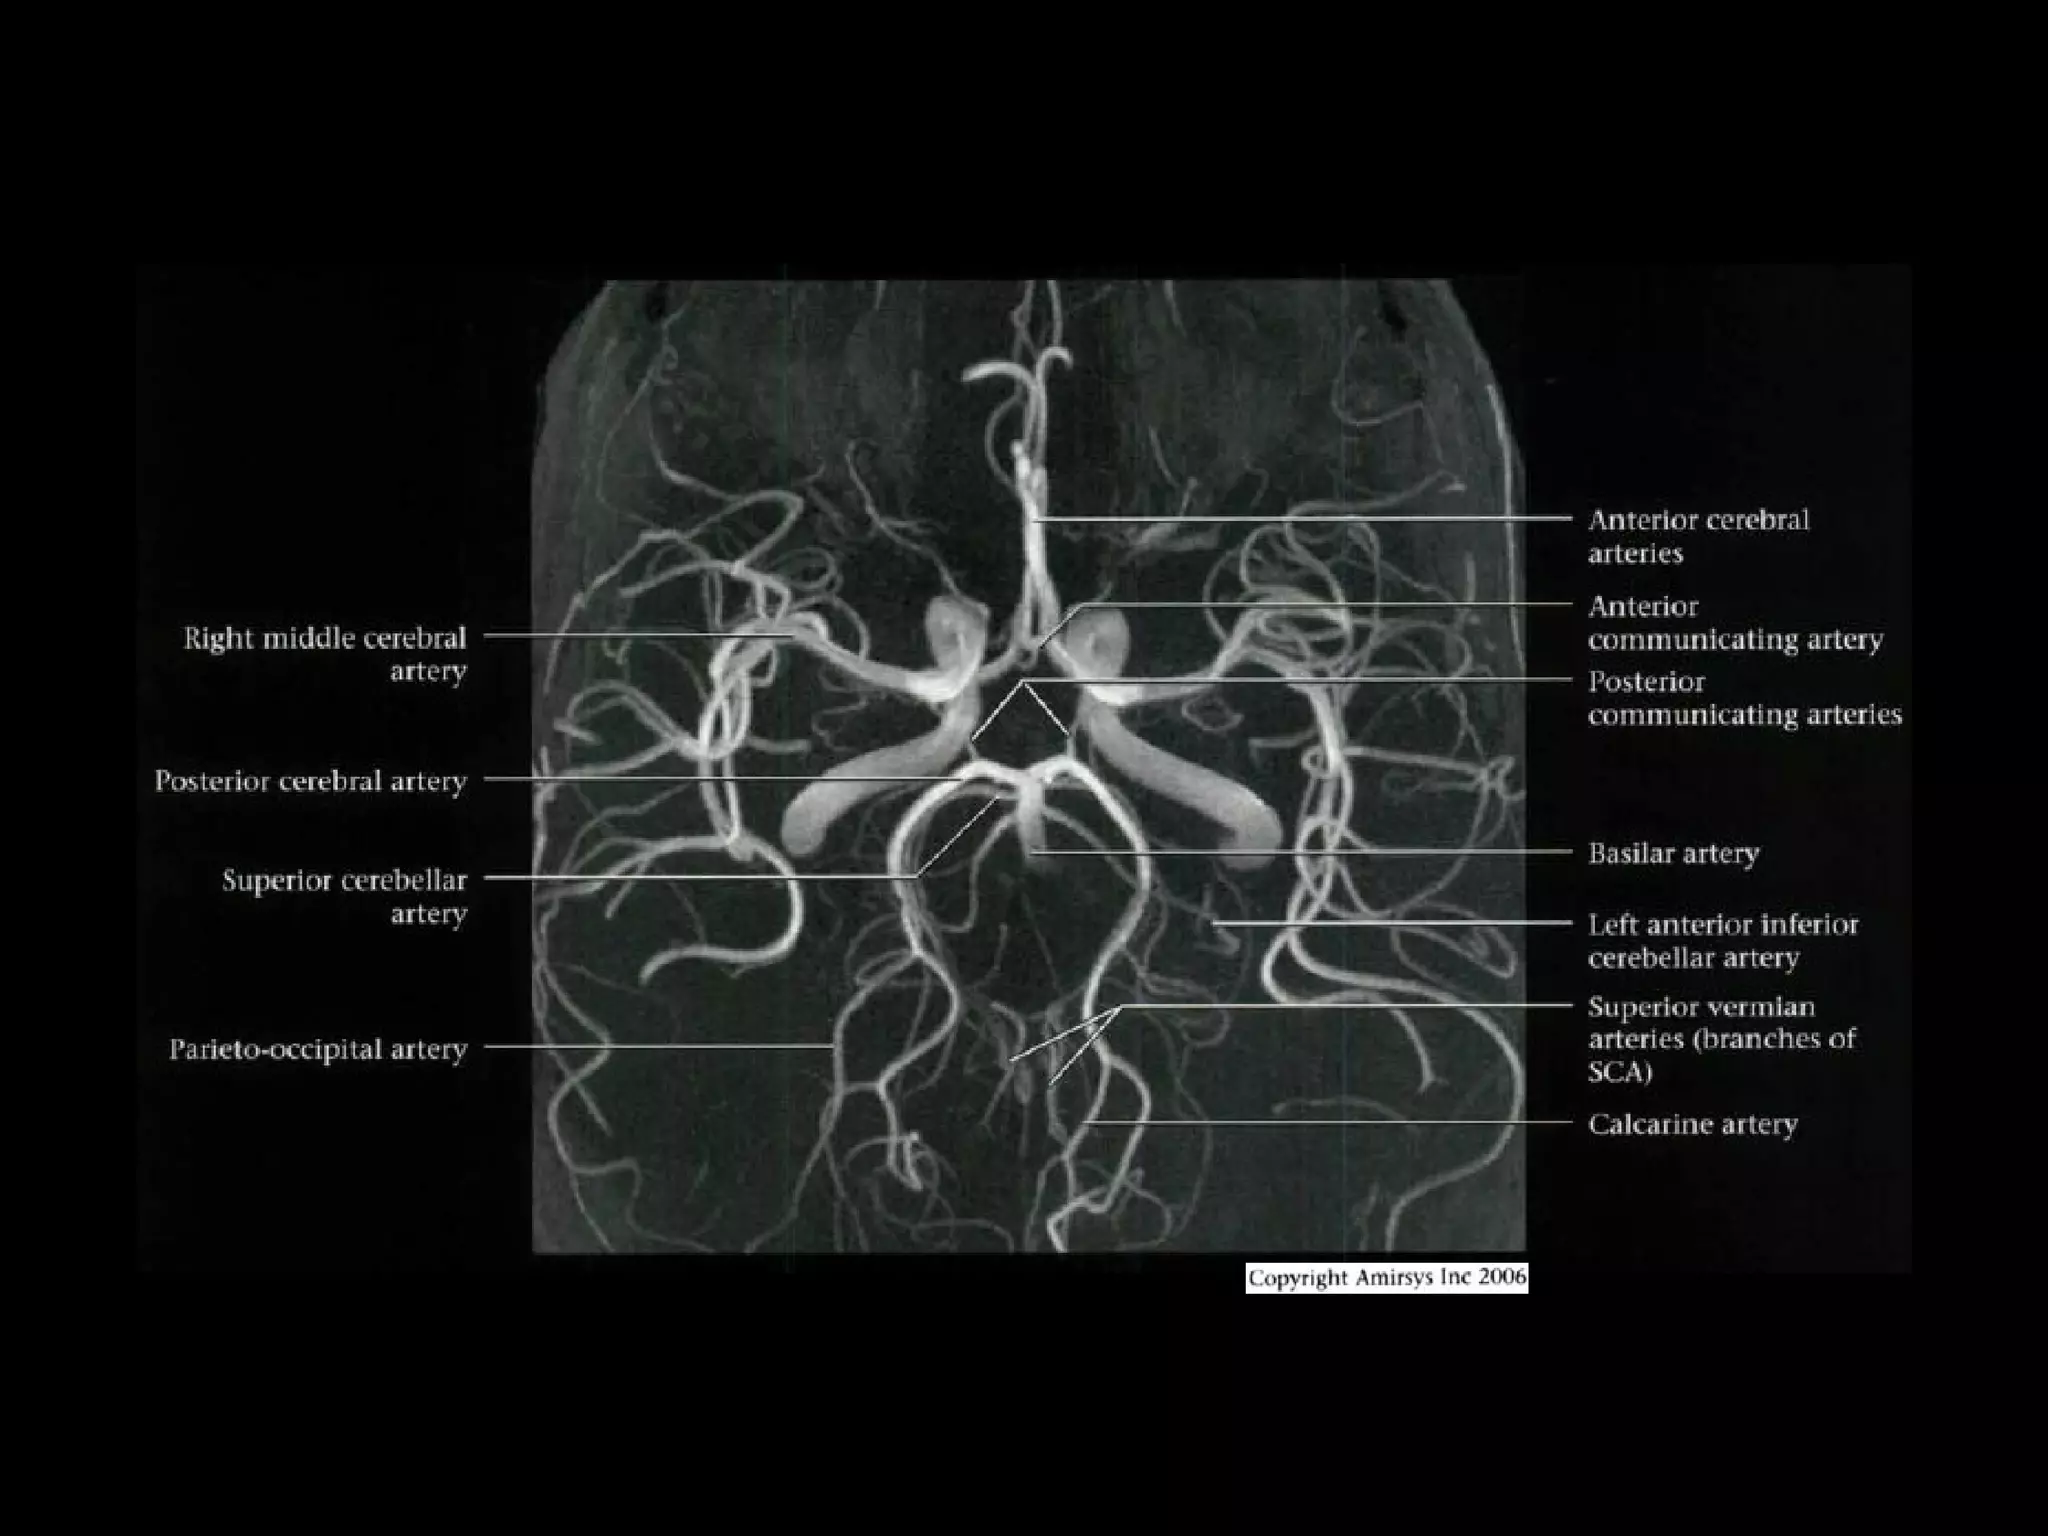

Gross Anatomy

• Anterior Circulation

• Posterior Circulation

- Basilar artery and its branches

Basilar Artery

•

Courses cephalad in prepontine cistern to terminal bifurcation

ventral to midbrain

- Gives off AICA, superior cerebellar arteries (SCAs), pontine,

midbrain perforating arteries

• Bifurcates into POSTERIOR CEREBRAL ARTERIES, each of

which has 4 segments

- Mesencephalic or pre communicating (P1) segment lies within

interpeduncular cistern, curves posterolaterally from BA to PCoA

junction

- Ambient (P2) segment extends from PCA-PCoA junction, curving

around cerebral peduncles just above tentorium, above oculomotor

nerve

- Quadrigeminal (P3) segment extends posteromedially from level

of quadrigeminal plate

- Cortical (P4) branches arise from distal PCA at or just before

reaching calcarine fissure

- Perforating branches arise from P1

• Vertebral arteries